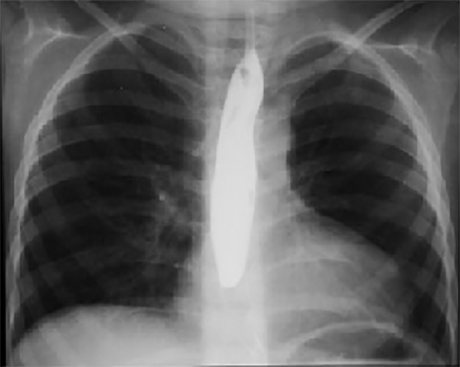

This chest X ray taken during a barium swallow shows right ventricular enlargement, a small pulmonary trunk, increased pulmonary arterial vascularity and a left aortic arch.

Right ventricular enlargement is demonstrated by the upturned cardiac apex. Decreased size of the pulmonary trunk is suggested by the straight left cardiac silhouette. Increased pulmonary arterial vascularity is reflected by dilated central pulmonary arteries. A left aortic arch is indicated by deviation of the tracheal air shadow to the right and presence of the aortic knob at the left upper mediastinal border.